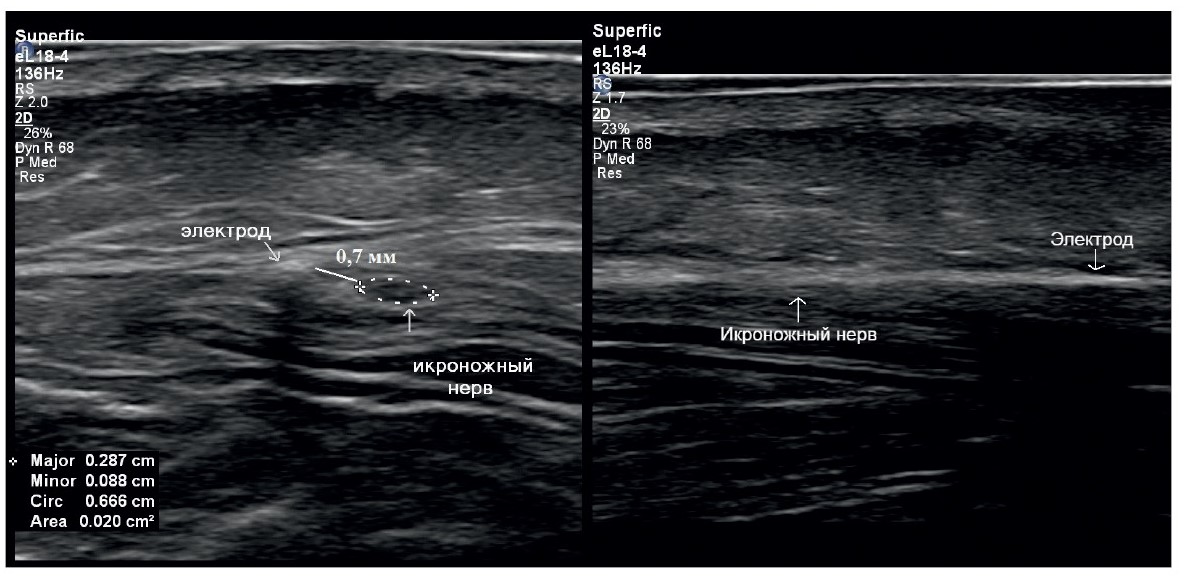

In 2023, the patient presented to the N.N. Burdenko National Medical Research Center of Neurosurgery, where she underwent a sural nerve block. Complete regression of the pain syndrome was observed during the local anesthetic effect, with complete recurrence of pain occurring on days 2–3 post-block. Consequently, a decision was made to implant an electrode for chronic electrical stimulation of the n. suralis under ultrasound guidance. A 3 cm linear incision was made on the posterolateral surface of the calf, through which the n. suralis trunk was identified under ultrasound guidance. Using a Tuohy epidural needle (provided with the electrode kit), the electrode was implanted parallel to the n. suralis course and secured at the incision site with a thick non-absorbable silk suture (5 metric) (Figs. 2, 3).

Fig. 3. Ultrasound image of the implanted electrode.

Left: transverse scan. The electrode runs along the trunk of the sural nerve (n. suralis) at a distance of less than 1 mm from it. Right: longitudinal scan. Aligning the electrode and n. suralis in the same plane is extremely challenging due to their spatial relationship, but the electrode shadow and epineurium of n. suralis can be visualized.